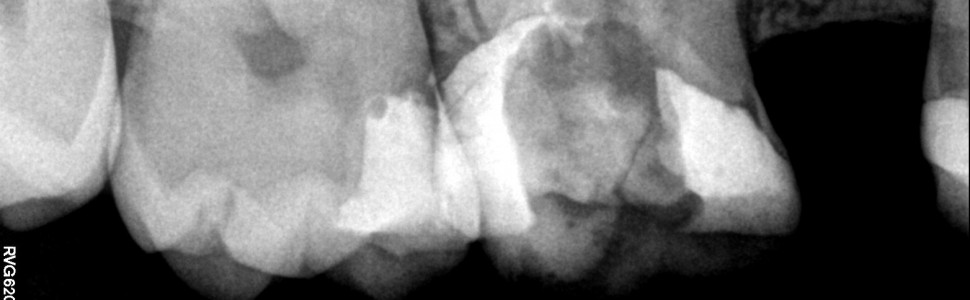

Do wizyty w gabinecie skłoniło pacjenta pobolewanie zęba, trwające od kilku tygodni, stale przybierające na sile. Pacjent nie gorączkował. Wykonano zdjęcie punktowe (ryc. 1), na którym stwierdzono obecność zmiany okołowierzchołkowej i niewłaściwie przeprowadzone, kilka lat wcześniej, leczenie kanałowe. Rozpoznanie wstępne wskazywało na przewlekłe ziarninowe zapalenie tkanek okołowierzchołkowych.

Ryc. 1. Zdjęcie zęba 16 przed leczeniem wykonane w systemie radiografii cyfrowej.